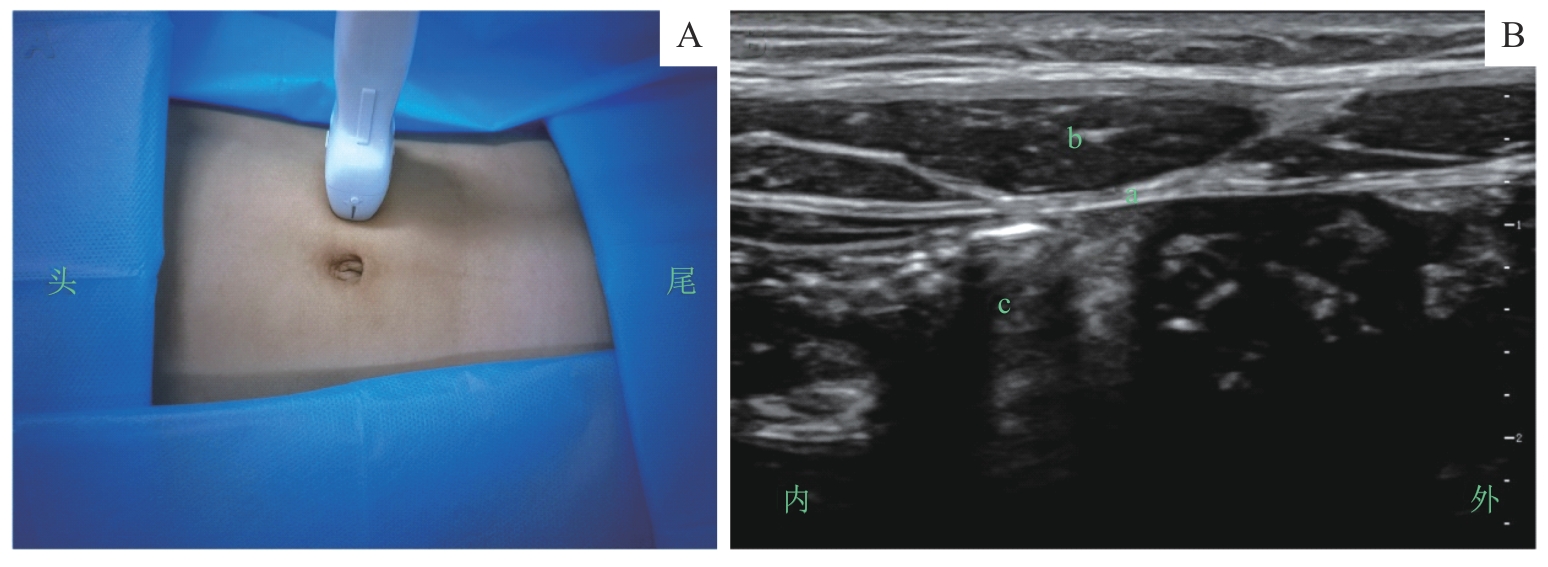

图5 腹直肌鞘阻滞的超声定位和影像Note: A. 超声探头体表扫描定位/Surface scanning for ultrasound probe positioning. B. 探头处于图A位置时的腹直肌鞘超声影像/Ultrasound image of the rectus sheath obtained with the probe positioned as shown in figure A. a—腹直肌后鞘/posterior sheath of rectus abdominis muscle; b—腹直肌/rectus abdominis muscle; c—腹腔/abdominal cavity.

Fig 5 Ultrasound positioning and imaging of the rectus sheath block